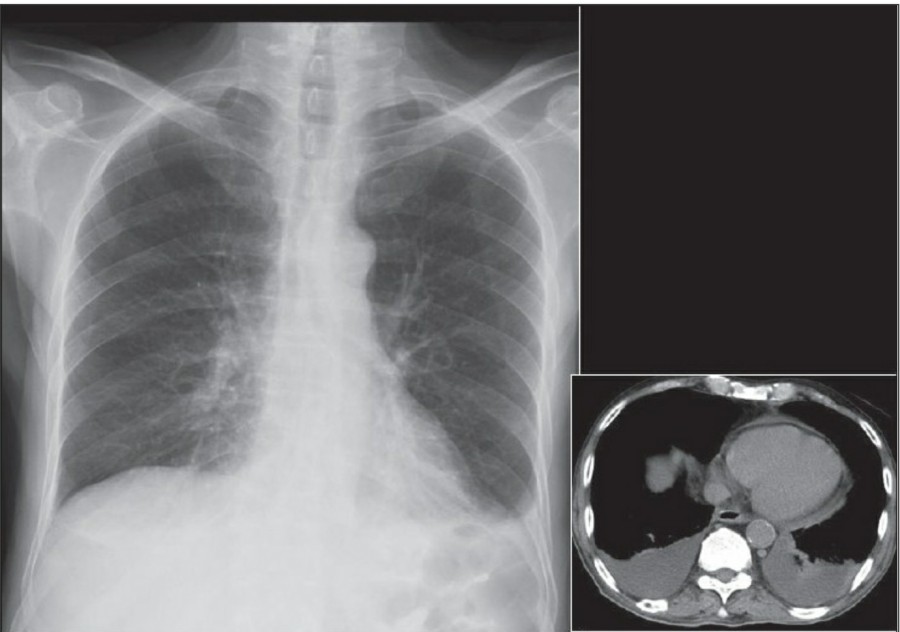

방사선 소견상 Pleural effusion은 환자 흉부의 dependent area에 고인다. Erect position에서 확인하기가 쉬운데, 폐의 base에 고임으로써 costophrenic angle blunting을 보이고 lower lobe vessel들의 흐리게 한다. Supine position에서는 확인이 더 어려운데, pleural fluid는 posterior basilar space에 고여서 폐 base 쪽으로 intensity가 증가하는 homogenous density를 보인다. 정상적인 bronchoalveolar marking은 이와 같은 veil-like density 안에서 확인 가능하다. Fluid 양이 늘어나면서 diaphragm의 윤곽이 흐릿해지고 costophrenic angle도 없어지는데, 이 costophrenic angle blunting이 없더라도 pleural space에 1L 정도의 pleural fluid가 있을 수 있다는 것을 기억해야 한다. 그 양이 더욱 늘어날 수록 fluid는 lung의 apex에서 pleural cap으로 나타날 수 있으며, 이는 supine position에서도 확인 가능하다. Pleural fluid는 lung의 medial side에 고일 수도 있으며 이는 mediastinum의 확장으로 보일 수도 있다.

적은 양의 pleural fluid는 꼼꼼히 확인하더라도 supine radiograph에서 놓칠 수 있는데, 만약 chest X ray에서 보이지 않지만 임상적으로 의심이 되는 경우에는 lateral decubitus film으로 확인해 볼 수 있다. Fluid는 dependent position에 고이므로 환자를 의심되는 방향으로 옆으로 눕혀야 한다. Lateral decubitus film은 적은 양의 pleural fluiid는 물론이고 loculated effusion과 free effusion을 확진하는 데도 도움이 된다. 특히 loculated effusion은 한 개 이상의 drain이 필요할 수 있으므로 pleural drainage를 고려할 때 특히 중요한 검사이다. 중환자에서 흔하게 나타나는 subplumonic effusion은 lung base에 존재하는 pleural effusion을 말하는데, chest X ray 상에서 raised hemidiaphragm with flattening and lateral displacement of the dome 형태로 나타나며, lateral decubitus film이 도움이 된다.